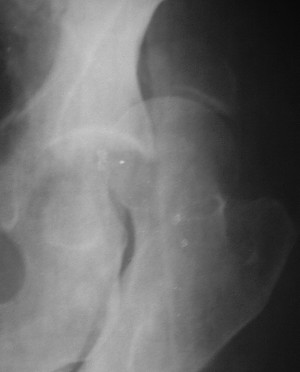

19/05/03

При поступлении в госпиталь 3.06.03

Больной 18 мая 2003 года в автоаварии получил перелом левой вертлужной впадины, вывих бедра. Госпитализирован в один из стационаров области.Вывих вправлен. В последствии бедро вывихивалось еще дважды. На консультацию был представлен снимок от 19.05.03г., больной переведен к нам 3.06.03г. Снимок при поступлении - перелом впадины, задне-верхний вывих бедра. 05.06.2003 г. выполнено открытое вправление вывиха левого бедра и остеосинтез стенки вертлужной впадины двумя винтами. Послеоперационный период без осложнений. Объем движений в левом тазобедренном суставе восстановился полностью. Выписан на амбулаторное лечение в удовлетворительном состоянии с рекомендациями 3 месяца ходить на костылях без нагрузки на оперированную конечность. На контрольных рентгенограммах левого тазобедренного сустава 13.10.2003 г. - признаки консолидации перелома; плотность, форма головки и состояние суставных поверхностей удовлетворительные. Разрешена дозированная осевая нагрузка, на конечность с использованием дополнительной опоры. 19.12.2003 г. больной обратился с жалобами на боли в левом тазобедренном суставе. На рентгенограммах левого тазобедренного сустава 19.12.2003 г., 20.02.04г. - асептичекий некроз головки бедра. 5.04.04г. - эндопротез. Сейчас ходит без трости, не хромает. Особенность эндопротезирования - при удалении винтов прослежена линия перелома заднего края впадины и предложено установить чашку несколько меньшего диаметра, чтобы она была покрыта несломанной частью.